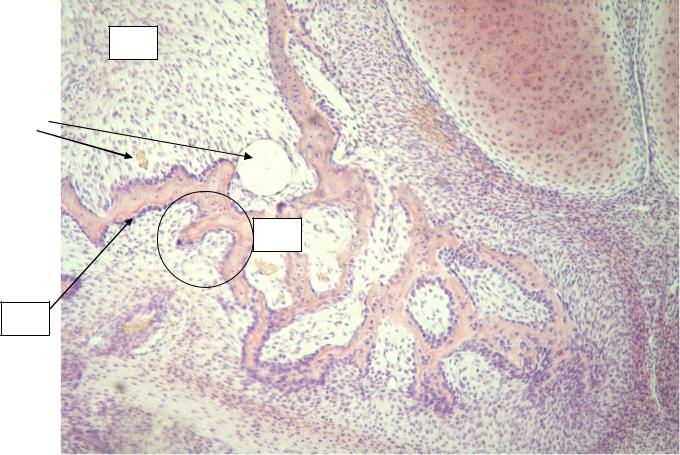

Структура грубоволокнистой костной ткани: наглядные примеры